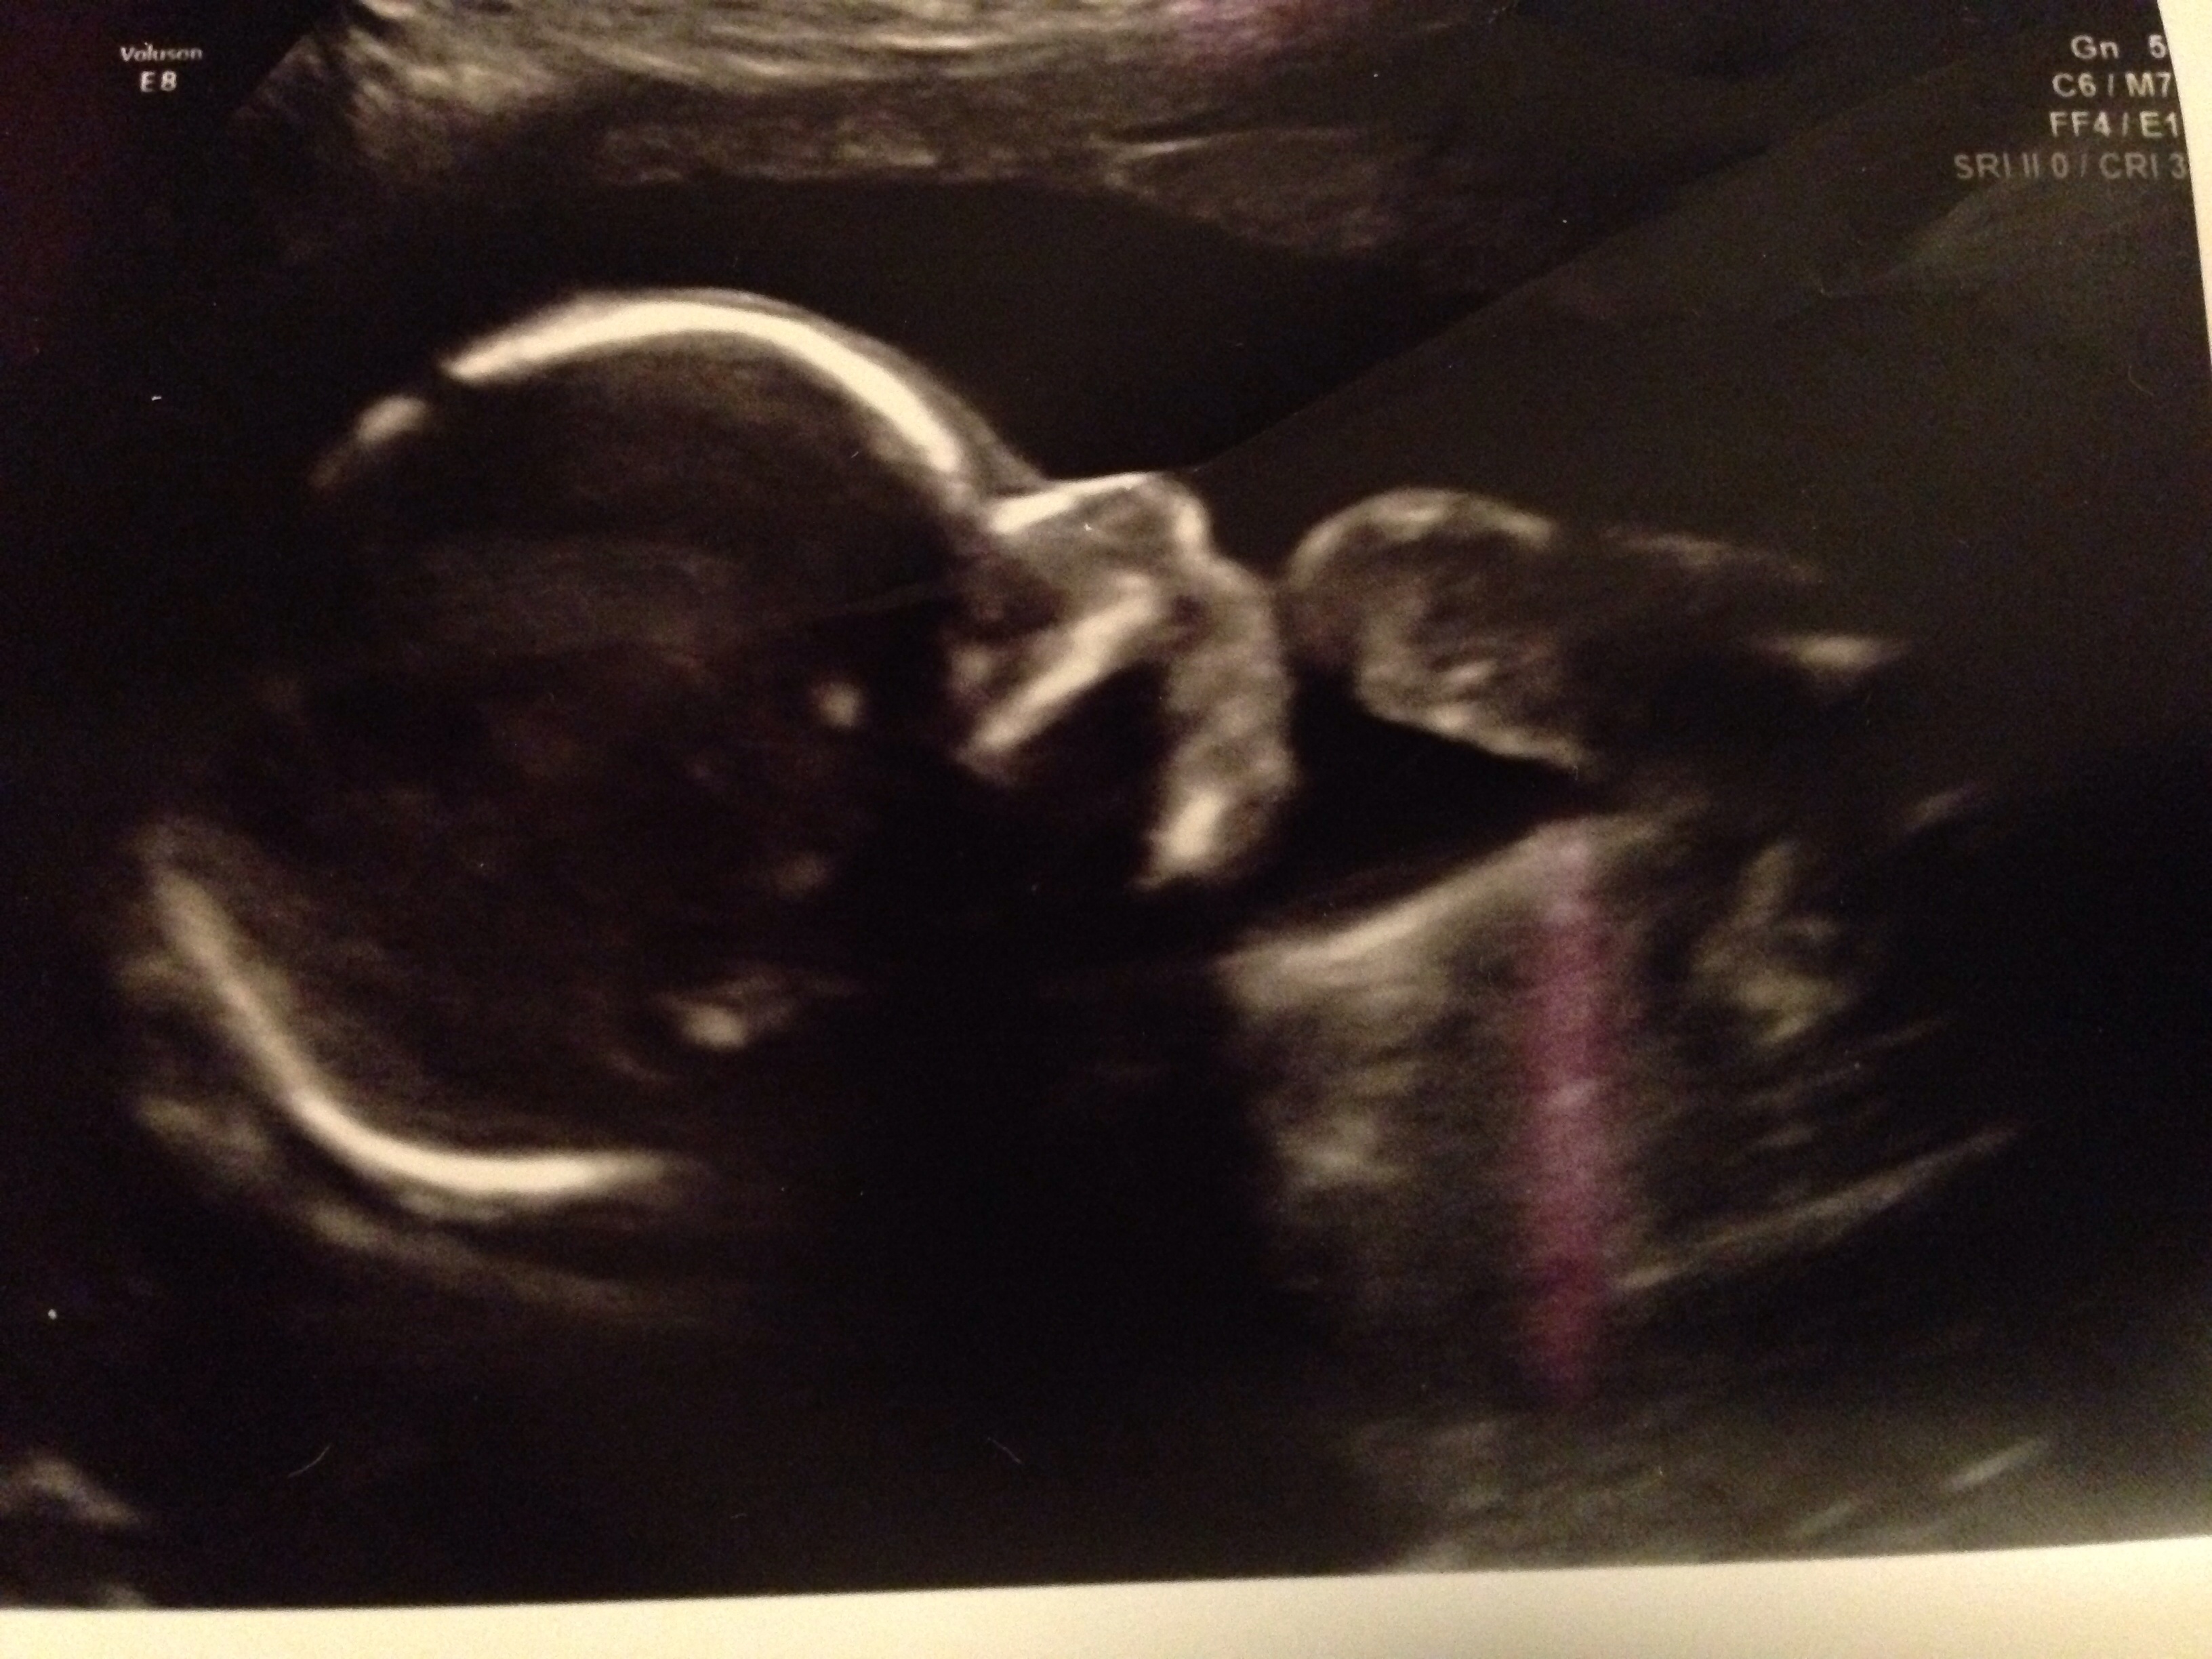

20w5d today (ticker is wrong but haven't updated it yet)

Here is our baby girl last Thursday at our a/s appointment. They found a cyst on her brain called Choroid Plexus Cyst so we have to see a perinatologist to have it looked at further to see if she possibly has Downs Syndrome since it is considered a soft marker. Dr was very positive about the outcome and said she had no other markers and that normally go away but it's just a precaution. Praying for the best! She just started kicking away a few days back and hubby has got to feel her twice already each on a different day. She is also sitting breech for now so hoping she uses the next 19 weeks to get into position : D